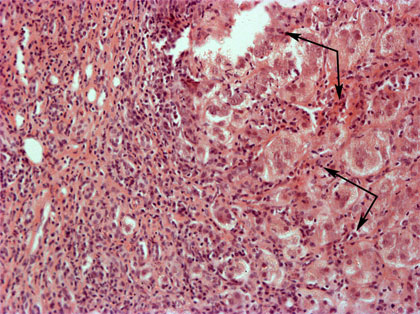

Krooninen maksatulehdus (Hepatitis chronica) 100x

Tulehdussolukko työntyy myös itse maksaparenkyymiin (nuolet). Tyypillistä tulehdusreaktiolle on ns. nakerrus-nekroosi, jossa raja portaalikentän ja maksaparenkyymin välillä on tulehdusreaktion johdosta epätarkka. 100x suurennos, HE-värjäys.